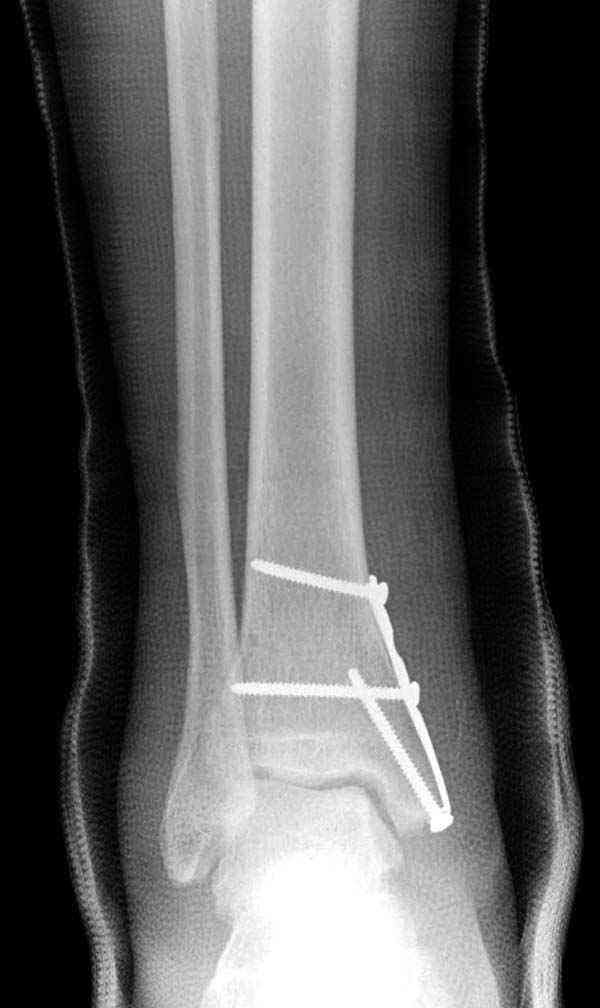

Нет первичных снимков, перелом очень низкий и под большим сомнением диагноз разрыва синдесмоза. Медиальная сторона отрепонирована на "хорошо" и, по-видимому, прорезание проволоки произошло во время операции. Без снимков трудно судить о высоте малоберцовой, а лодыжка находится в варусе. Лагирование получилось, но возле тонких шурупов передне-задний шуруп выглядит немного тяжеловато.

Во всех руководствах АО имеется описание техники применения низкопрофильных пластин 1/3 трубки, которые могут быть применены для фиксации наружной лодыжки. Фиксацию проводят кортикальными 3.5 мм шурупами, и если дистальная фиксация недостаточная, тогда усиливают конструкцию созданием hook plate. Сгибая конец пластины на последнем отверстии, внедряют его в дистальный отдел, и тем самым создается дополнительная фиксация.

Современные преконтурированные пластины не имеют таких недостатков, и разделяются на правые и левые, а также на латеральные и задние. Множественные дистальные шурупы 2.7 мм уменьшают подкожное раздражение, и такой имплант можно оставить на долгий срок без удаления.

Для молодых достаточным бывает обычная лодыжечная пластина без блокировки, и только у пожилых с остеопорозом лучше взять полиаксиальные пластины с угловой стабильностью.

Медиальная лодыжка фиксируется каннюлированными лодыжечными шурупами перкутанно, а неточная репозиция (интерпозиция) является показанием к открытой технике. При больших вертикальных фрагментах нужны противоскользящие медиальные пластины.

При лечении синдесмоза количество шурупов не имеет значения. Два через три кортекса или один через все кортикальные слои механически одинаковы.

Здесь несколько частных случаев: перелом голеностопа со сравнительными снимками и разрыв синдесмоза, а также медиальная Hook пластина.